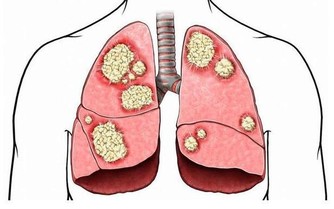

如果不想上火,平時在日常生活中就不應該吃一些辛辣和油膩的食物,有些人一到晚上就喜歡出去吃火鍋或者是吃燒烤,這些夜宵不僅對人體的腸胃功能有巨大的損害,還會讓人上火。

食物在經過燒烤之後,裡面的一些營養物質都會變成強烈的致癌物質,所以這些東西是不能夠經常吃的。晚上吃夜宵一定要選擇健康的食品,比如說喝一兩碗粥或者是吃一點兒水果就行了,千萬不要吃火鍋,或者是燒烤這些東西不僅辛辣,並且油膩特別容易讓人上火。